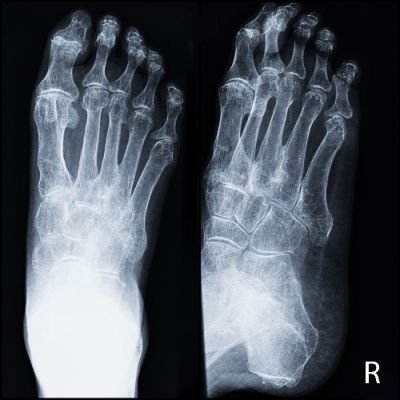

Osteopenia is a bone condition characterized by lower-than-normal bone mineral density (BMD), but not to the extent seen in osteoporosis. When osteopenia specifically affects the bones in the foot, it poses unique challenges and considerations.

Bone mineral density is a measure of the amount of minerals—such as calcium and phosphorus—in bone tissue. In osteopenia, the density is reduced, making the bones more susceptible to fractures and injuries.

Due to reduced bone density, individuals with osteopenia in the foot are at a higher risk of fractures and stress injuries. Stress fractures, particularly in the metatarsal bones, are common in this population.

A DEXA scan is a non-invasive and widely used method to measure bone density. It provides a T-score, comparing an individual's bone density to that of a healthy young adult.

pQCT is another imaging technique that can assess bone density specifically in the foot. It offers detailed information about the structure and composition of bones in this region.